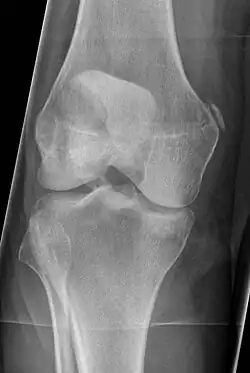

Pellegrini–Stieda syndrome (also called Stieda disease and Köhler–Pellegrini–Stieda disease) is the ossification of the superior part of the medial collateral ligament of the knee. It is a common incidental finding on knee radiographs. It is named for the Italian surgeon A. Pellegrini (b. 1877) and the German surgeon A. Stieda (1869–1945).[1] While the eponym refers to Pellegrini and Stieda, the condition was first discovered by Köhler in 1903, before any namesakes. Pellegrini-Stieda combines the aforementioned radiographic findings and concomitant medial knee joint pain or restricted range of motion.[2]

Diagnosis is typically made on radiographs demonstrating the Pellegrini-Stieda syndrome sign accompanied by pain or restriction of range-of-motion of the knee joint.[2] Pellegrini-Stieda syndrome sign is typically described by a longitudinally linear opacity, which is a process that is describes characteristic of calcification in the soft tissue located medial to the medial femoral condyle.[2] This calcification seen on imaging represents the ossification of the medial collateral ligament, which typically does not develop until approximately three weeks after the initial injury.[2]It is important to note to distinguish this radiographic finding from that of a medial femoral condyle avulsion fracture, which is an injury in which a pulling force of a tendon or ligament fractures away a piece of the bone from its attachment site.[2]

The Pellegrini-Stieda syndrome is a relatively infrequent phenomenon and is commonly associated with sporting injuries. Pellegrini-Stieda Syndrome Is more frequent in the males between 25 and 40 years of age. Direct trauma or in a distant site (skull or spine), repetitive trauma, or after an overstretching injury to the medial collateral ligament and joint capsule can result in an avulsion of the medial femoral condyle or a tear of ligaments, tendons. Ossification could happen within 11 days to 6 weeks after post trauma. A network of the new bone formation around the periphery of the mass of the medial condyle is formed in 6 to 8 weeks. Duration of the condition is usually about 5 to 6 months.[4]